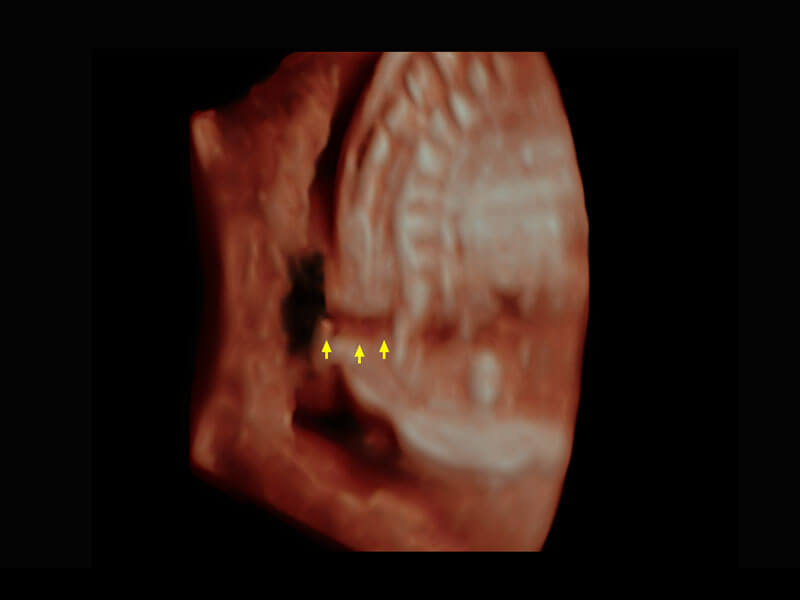

P60優(yōu)異的圖像質(zhì)量搭載??铺筋^,在婦科基礎(chǔ)疾病的診斷、卵泡生長的監(jiān)測、輸卵管通暢情況的判別等方面為您提供生殖應(yīng)用方案。

腔內(nèi)婦科-宮腔分離